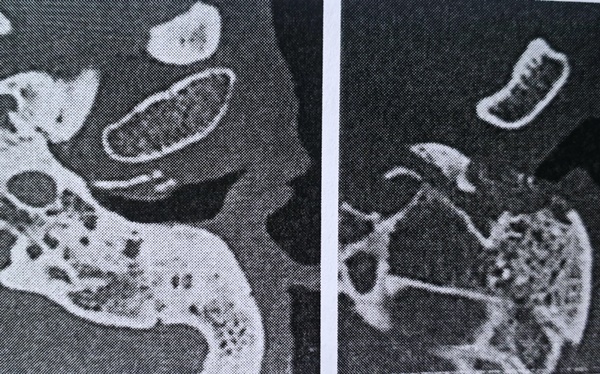

Một bệnh nhân viêm ttaingoài hoại tử có tình trạng hủy xương thành trước ống ttaingoài (Ảnh: BV).

Về dấu hiệu lâm sàng, đau ttailà triệu chứng thường gặp nhất, tiếp theo là cchảyttai,mmôhhạtviêm ống ttaingoài. Đáng chú ý, có 17 người bị liệt mặt ngoại biên. Về hình ảnh học, tất cả các bệnh nhân đều có tình trạng hủy xương ống ttaingoài và viêm lan vào ttaigiữa.

Trong đó, có 10 trường hợp viêm lan lên đến sàn sọ, 6 trường hợp viêm lan vào trong vòm hầu giữa. Ngoài ra còn có những ca viêm lan xuống dưới mỏm chũm, đỉnh xương đá… Có 2 trường hợp điếc sâu.